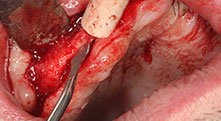

¿Podría describirnos brevemente cómo procede, por ejemplo, a la hora de mover injertos óseos destinados a trasplantes?

Bratu: Preferimos realizar las osteotomías en la línea oblicua externa de la cara posterior del maxilar inferior, y no en la región situada entre los orificios. Tras realizar una incisión en los tejidos blandos, utilizamos las nuevas sierras para definir el contorno de la osteotomía. De este modo, conseguimos una preparación completa en prácticamente el 80 por ciento de los casos. Por otro lado, en algunas ocasiones también utilizamos otros insertos piezoquirúrgicos, así como un cincel para mover el injerto. Para nosotros, esta es una técnica de intervención muy eficaz.

Bratu: Nos gusta utilizar la técnica de sándwich para realizar aumentos en la cara lateral del maxilar inferior. En este procedimiento, se utiliza la sierra piezoquirúrgica para preparar una tapa ósea, mientras que el fragmento crestal se fija con microtornillos. Entre medias, colocamos una combinación de hueso autólogo y material óseo adicional xenógeno. Y con ello obtenemos un rendimiento muy fiable. Asimismo, en los ranurados de la cresta alveolar del maxilar inferior, nunca se puede prescindir de cortes verticales suficientemente dimensionados, pues, de lo contrario, los huesos pueden fracturarse fácilmente.